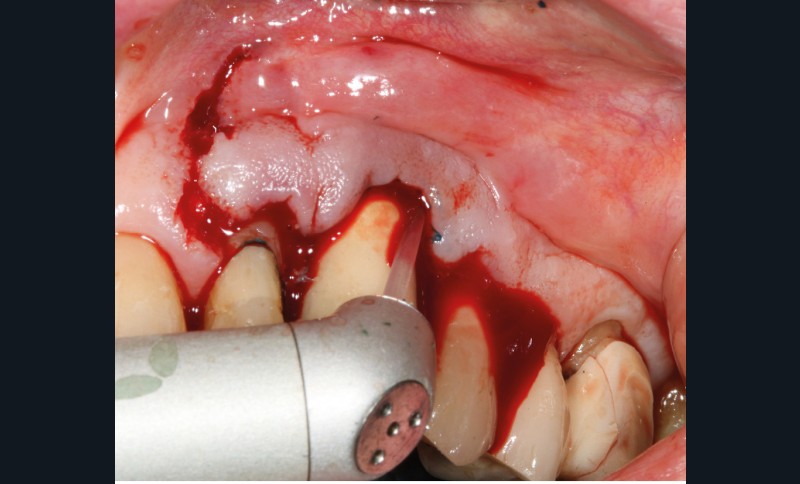

Le patient

- 70 ans

- Pas d’antécédents médicaux

- Ne fume pas

- Hygiène correcte

L’implant

- Site 23

- Mis en place il y a 12 ans